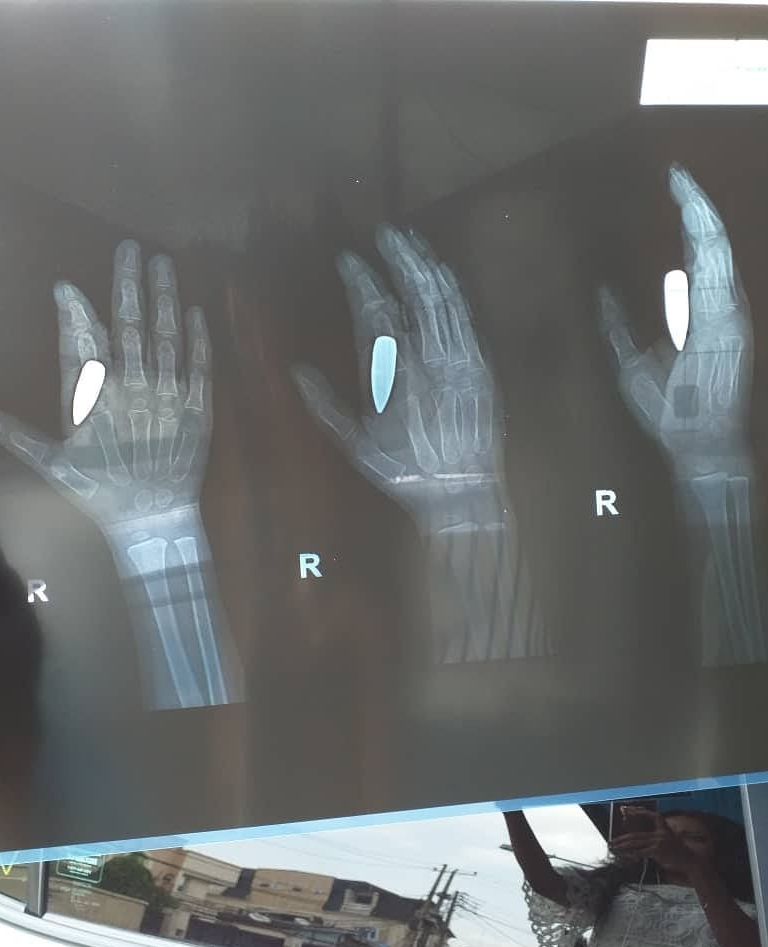

Okay y’all must have seen me post one or two things about my boy, Rocky. The incident happened on the 7th of February, I just got back from work when I heard him scream so loud. I rushed out and saw him crying and holding his right hand. We all thought something had cut his hand maybe while he was playing with the cup he was using to drink water. We rushed him to a local Bone doctor close to the house. The man did his best to adjust the bone and asked us to wait till the wound heals then we can come to fix the bone properly. All these while we thought we were treating bone. Not until few days ago we decided to do a scan and we found out a stray bullet almost hit this boy somewhere else but instead of hitting somewhere else, it hit his hand. We just did a minor surgery yesterday and a bullet was taken out. It could only be God. God did this for us and we are forever grateful.